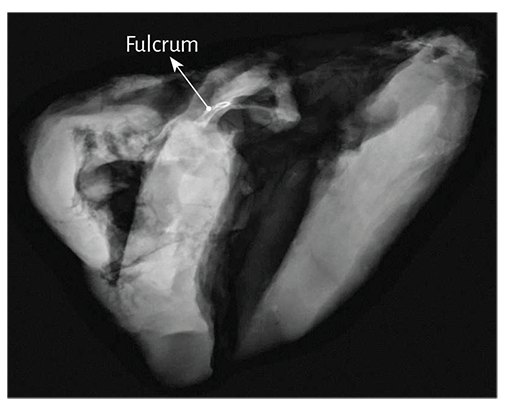

Figure 1.20. Resected cardiac fulcrum

(bovine heart).

Fulcrum imaging studies. Bovine hearts studied with computed tomography (Figures 1.40 to 1.42), magnetic resonance imaging (Figures 1.43 and 1.44) and X-rays (Figure 1.45) identified the osteochondral nucleus found in dissection, with the same morphology and analogous size.

Figure 1.45. Radiologic image of the cardiac fulcrum with mammography technique in the bovine heart.